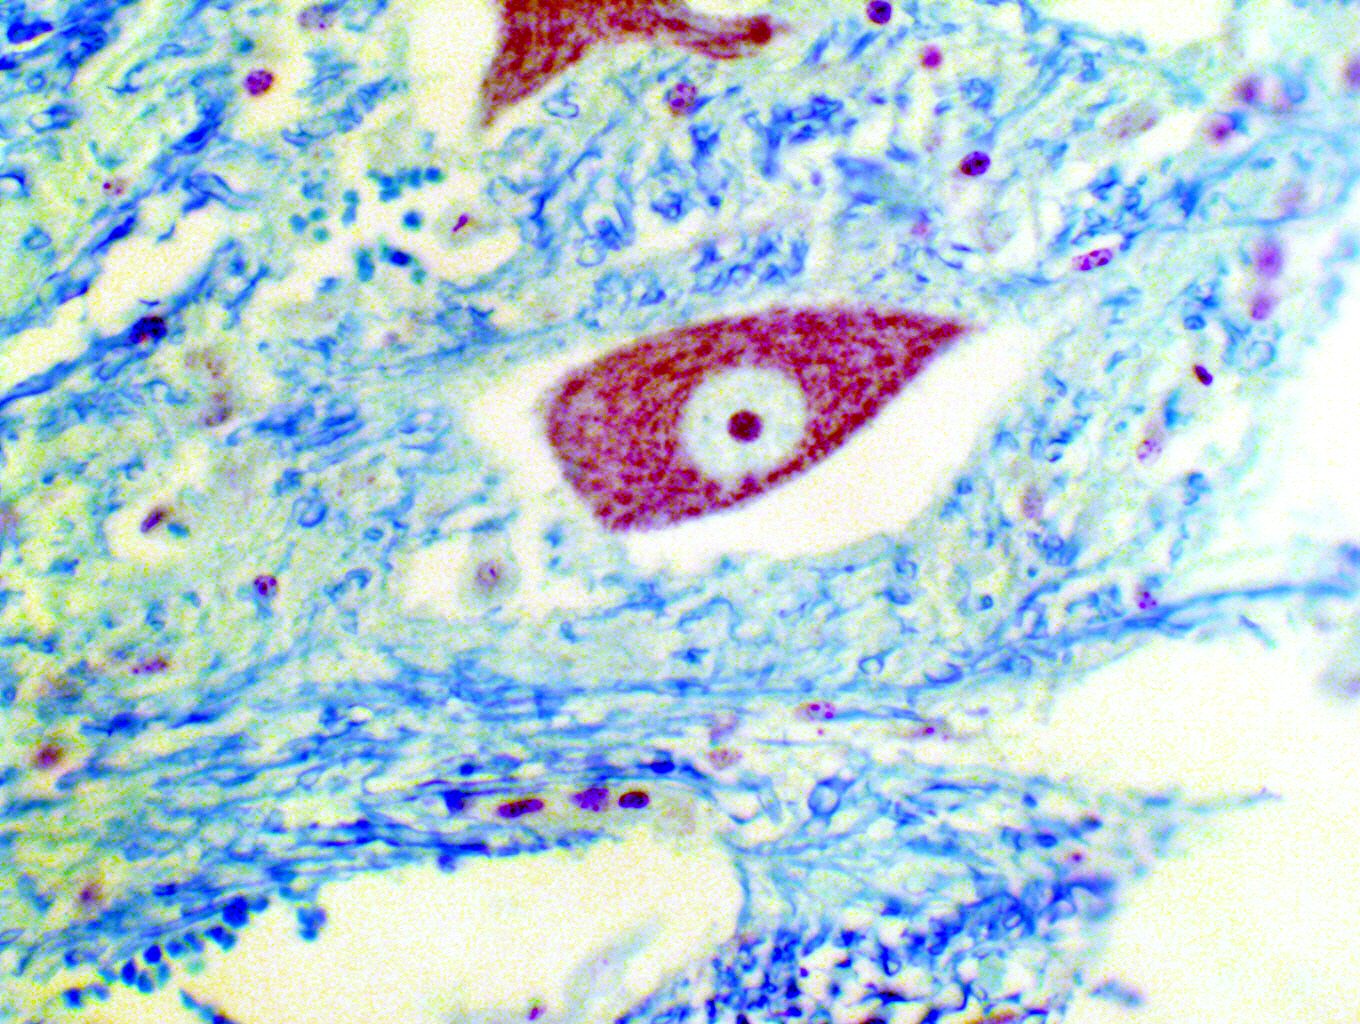

Luxol Fast Blue & Cresyl Violet

These two images illustrate another common stain used on nervous tissue: Luxol Fast Blue, which is often used with Cresyl Violet. The left image is a cross section of a nerve fiber tract: the LFB stain has highlighted the myelin sheaths of axons, and other nerve fibers. On the right, you can also see nerve fibers (this time in longitudinal section) and a large neuron as well, very nicely stained with the cresyl violet counterstain. Notice the large nucleolus and well-defined "Nissl bodies" in this neuron!Bovine Spinal Cord, 200x and 400x